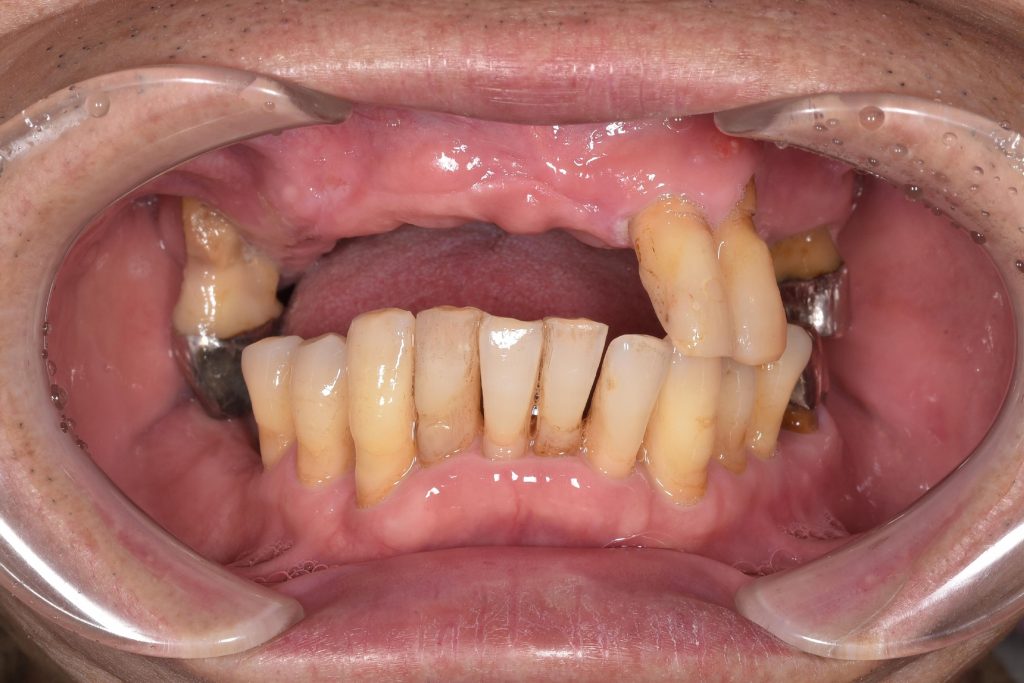

やはり、私が一番やりがいを感じるのは、患者様の笑顔であり、